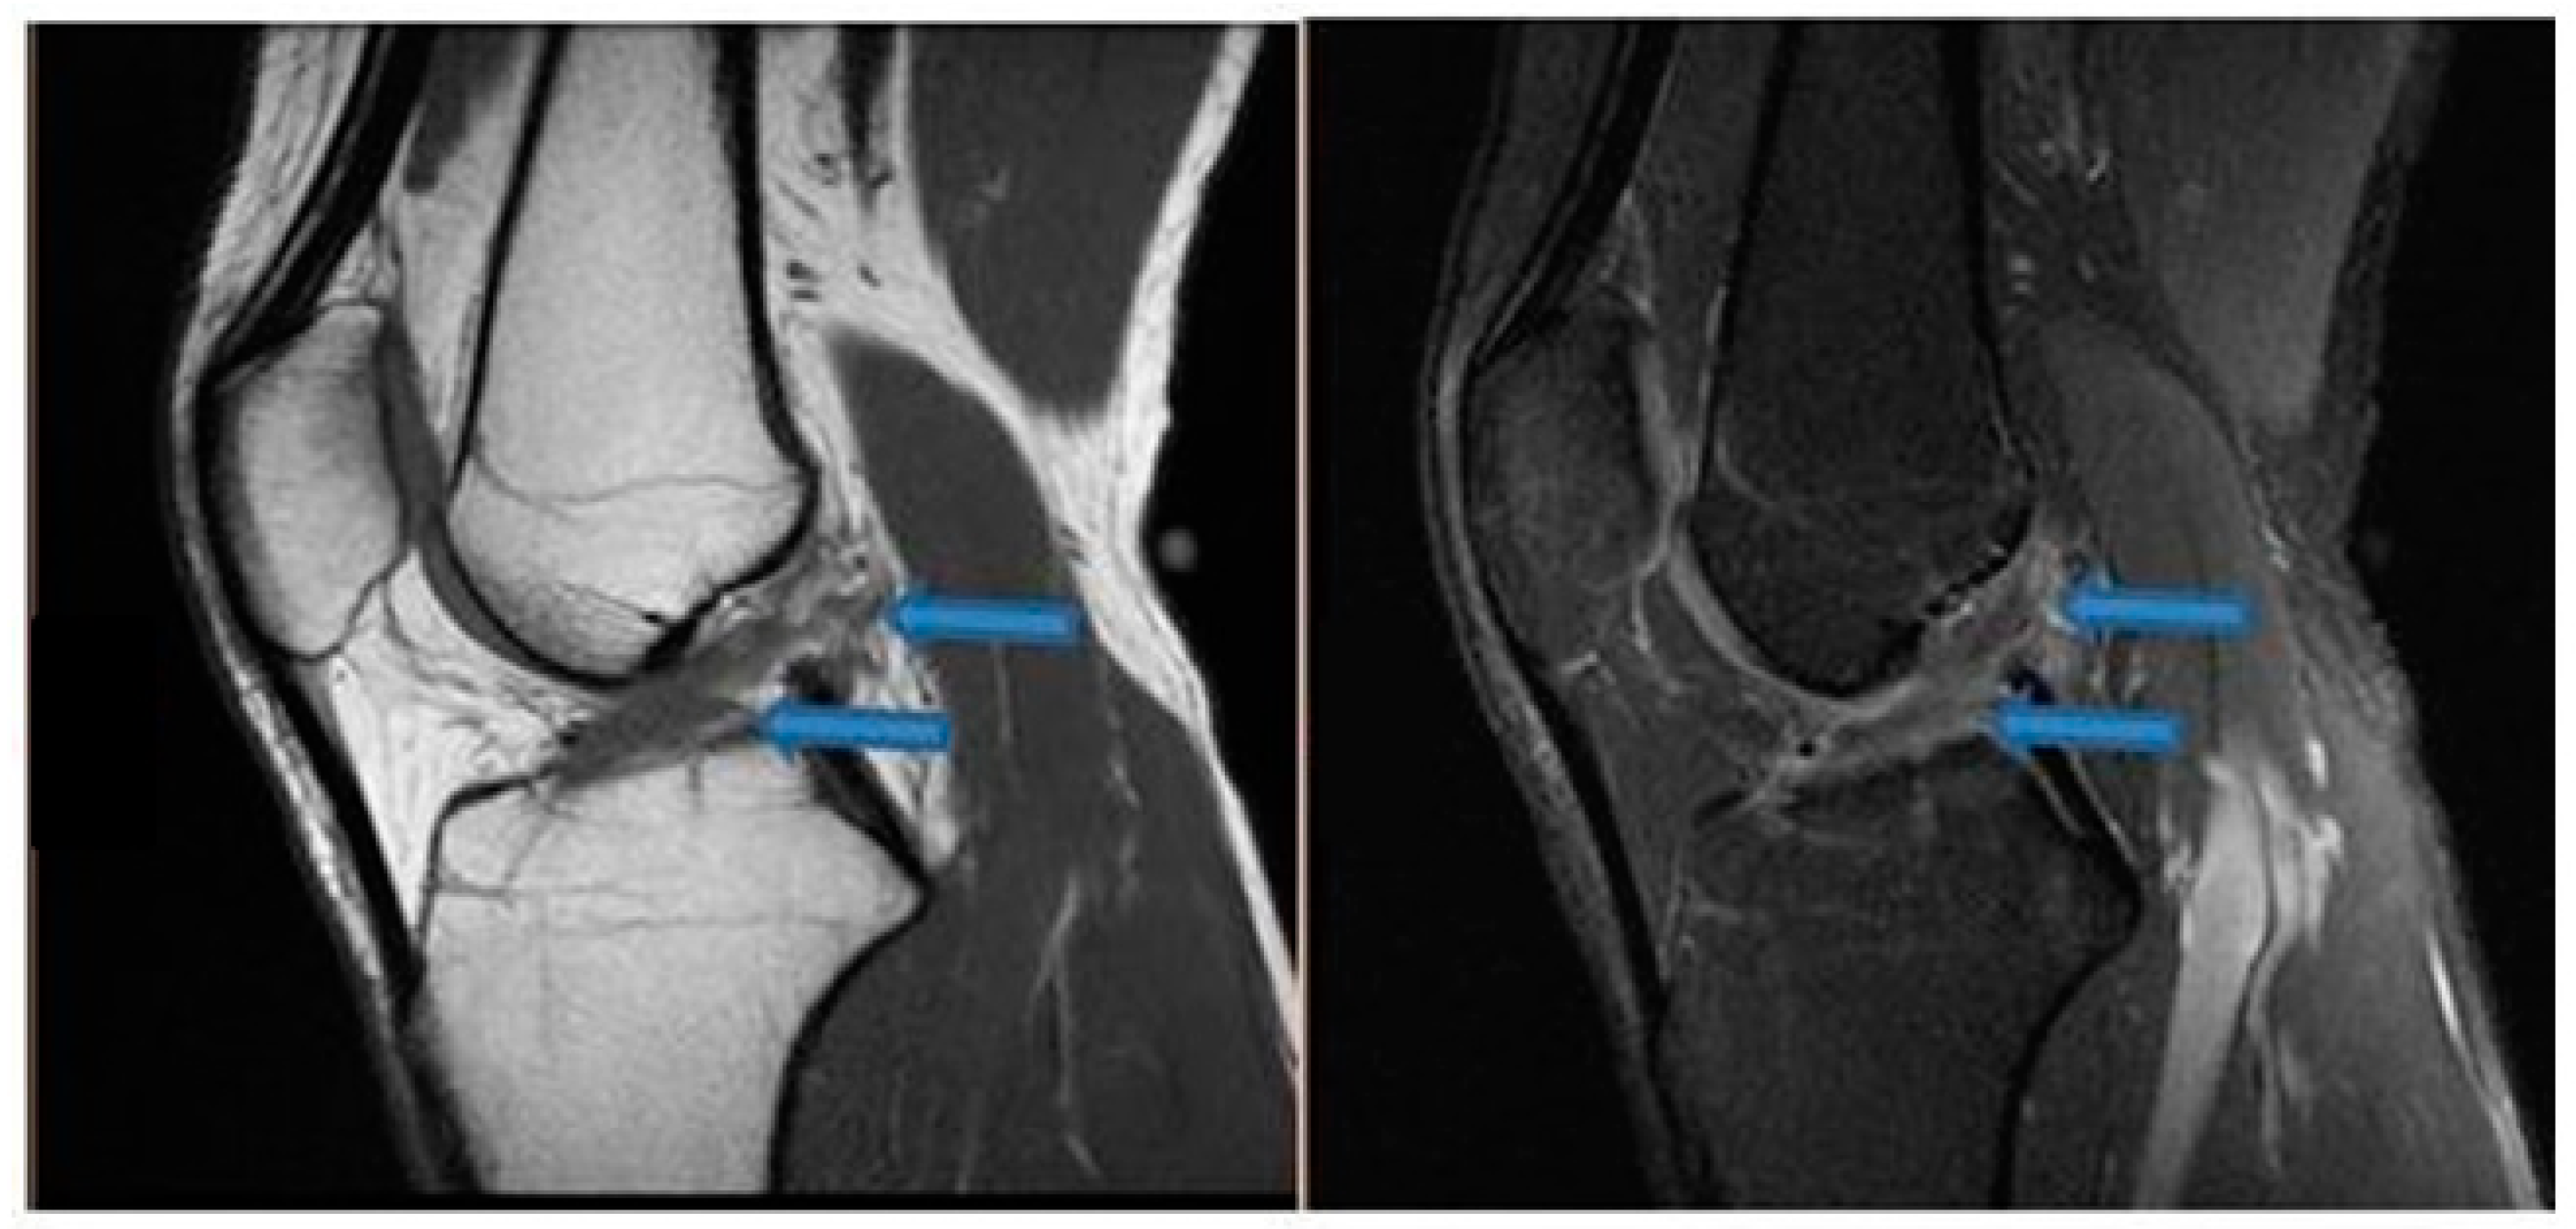

| 14 August 2021 | MRI scans demonstrating signs of complete ACL healing |